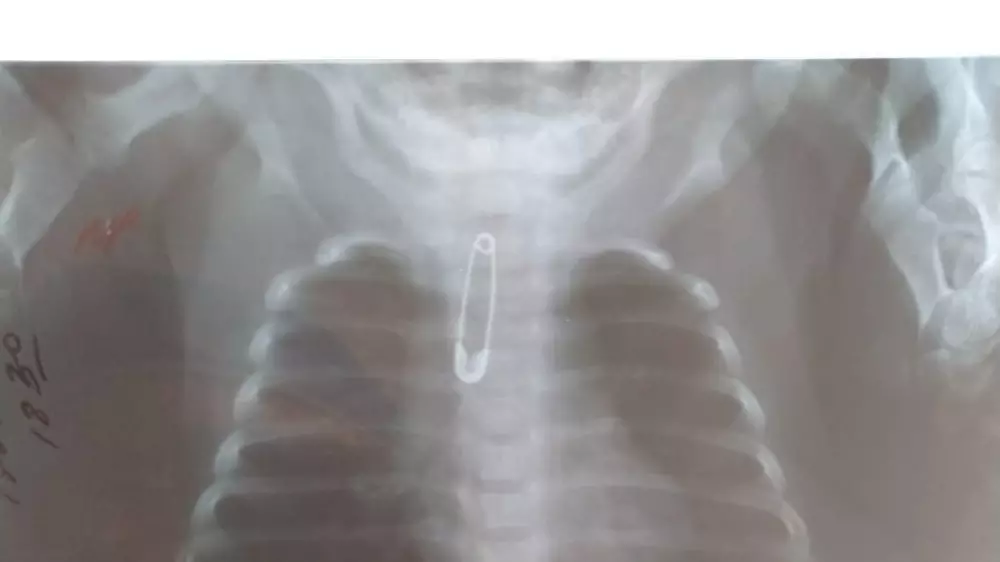

Сообщается, что булавку обнаружили в верхней трети трахеи. Для удаления опасного предмета в экстренном порядке маленького пациента прооперировали хирурги больницы Аким Тулкибаев, Нурбол Коянбаев, Берик Тотиков.

"Во время операции фибробронхоскопом была извлечена булавка. Операция прошла без разрезов. У ребенка хорошее общее состояние, в соответствии с протоколом он получает необходимое лечение", - сказал врач Аким Тюлькубаев.